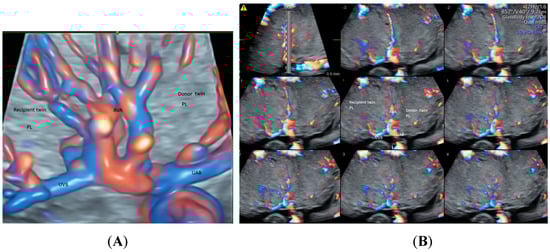

- Sun, W.; Chen, L.Z.; Yin, S.W.; Cai, A.L.; Yang, Z.Y. Non-invasive dynamic observation of placental vascular anastomoses in monochorionic twins: Assessment using three-dimensional sonography combined with tomographic ultrasound imaging. Placenta 2020, 95, 84–90. [Google Scholar] [CrossRef]

| Twin | Placental vascular anastomoses (HDFI) Intraplacental branches of umbilical artery (HDFI) | GBM TUI | Placental anastomoses in TTTS Different intraplacental vascularization in selective FGR TRAP, Cord entanglement in monoamniotic twin |